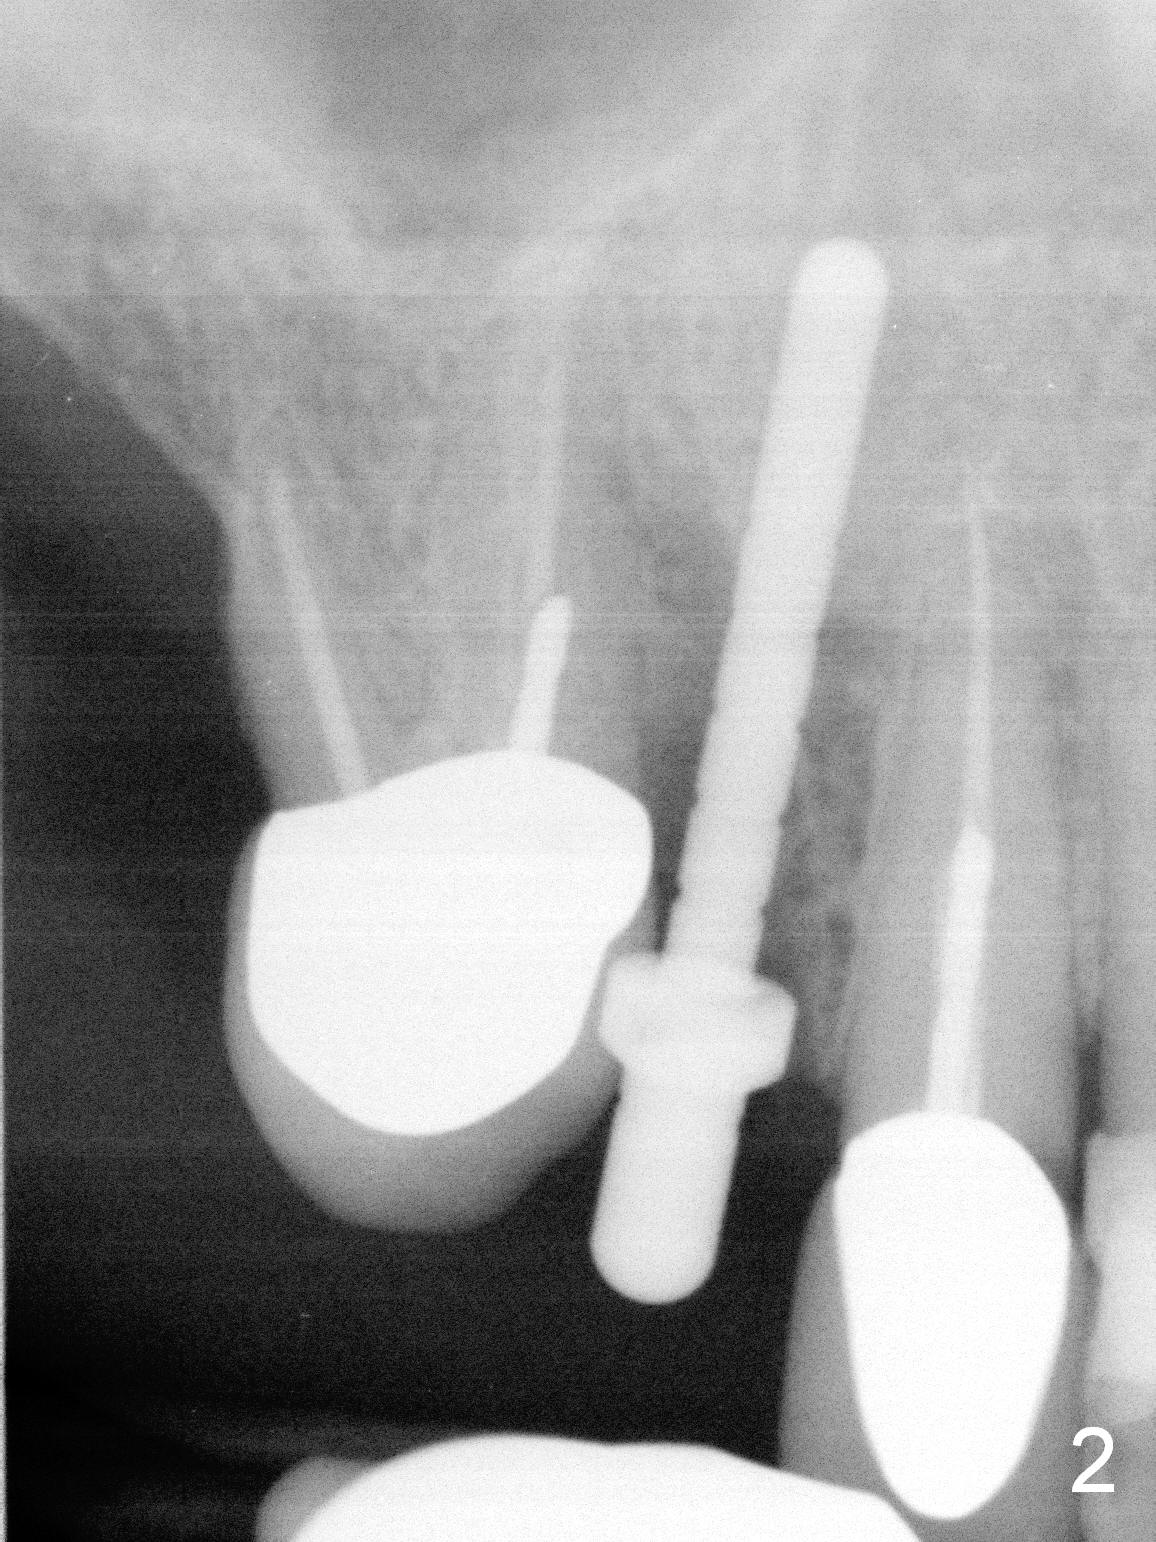

After extraction of the subgingival fractured upper right canine (Fig.1), the buccal plate is found to have been perforated at the apex. the root is measured 5x12 mm. Initial osteotomy with a 2 mm pilot drill shows that the bone is soft (Fig.2). After use of a 3.2 mm drill (underprep, normal drill size (3.7 mm)), a 4.5x15 mm implant is placed with insertion torque > 50 Ncm (Fig.3). The implant is further torqued until the implant plateau is 3 mm apical to the buccal gingival margin; a 5.5x5(3) mm abutment is placed (Fig.4,5 A). Osteogen plug is inserted into the apex of the socket, while the rest of gap is filled with mineralized cortical allograft and Osteogen. An immediate provisional (Fig.5,6 P) is fabricated to keep the graft in place, followed by periodontal dressing (Fig.6).